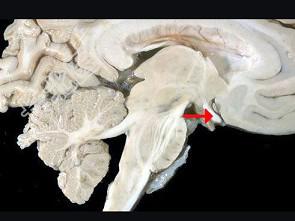

- 单项选择题如图箭头所示为视觉系统哪个部位 ( )

A、视束

B、视交叉

C、视不变

D、视乳头

E、视神经